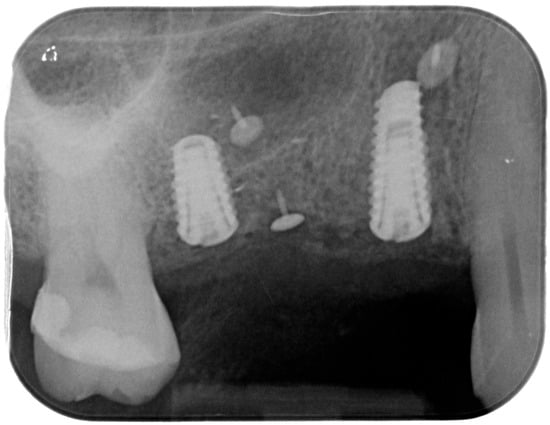

Figure 12. Intraoral X-ray at delivery of the final prosthesis.

For the evaluation of the mesial and distal MBL, intraoral digital radiographs were taken using the long-cone paralleling technique with the central beam directed to the alveolar crest. Periapical radiographs were taken at the delivery of the prosthesis and after 1 year of prosthetic loading (T2). The mesial and distal MBL, i.e., the distance between the top of the implant shoulder and the first visible bone-to-implant contact, were measured at the mesial and distal aspect with a 10–15× magnification using an image analysis programme (ImageJ v 1.49, NIH, Bethesda, MA, USA). The length of the implant was used as known measure for the calibration and determination of the exact magnification and distortion of the images. All measurements were performed by two examiners to the nearest 0.1 mm. In case of disagreement, the evaluation was re-done and results discussed until an agreement was found.